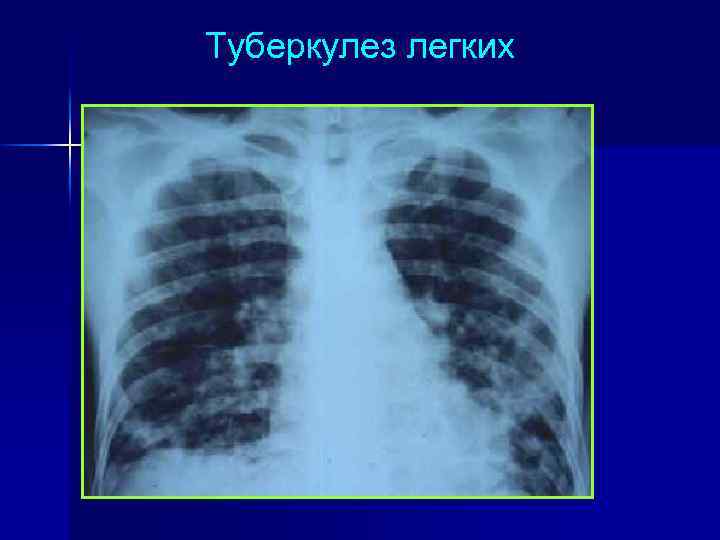

Туберкулез легких

Оппортунистические поражения легких у ВИЧ-инфицированных n n n Mycobacterium tuberculosis (при выраженной иммуносупрессии часты внелегочные формы – поражение костного мозга и л. у. ) Pneumocystis jiroveci (пневмония – лихорадка + сухой кашель + прогрессирующая одышка) Mycobacterium avium complex (пневмония) Toxoplasma gondii (пневмония) Cryptococcus neoformans (пневмония, плеврит) и другие грибковые пневмонии (Candida spp. , Aspergilla spp. ) Cytomegalovirus и др. герпетические вирусы (интерстициальная пневмония)